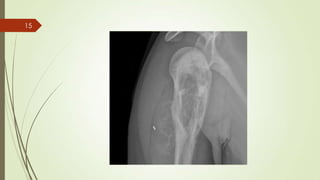

Imaging studies

 X ray : sun-burst" appearance and the apperance of Codman triangle.

sun-burst" appearance14

15